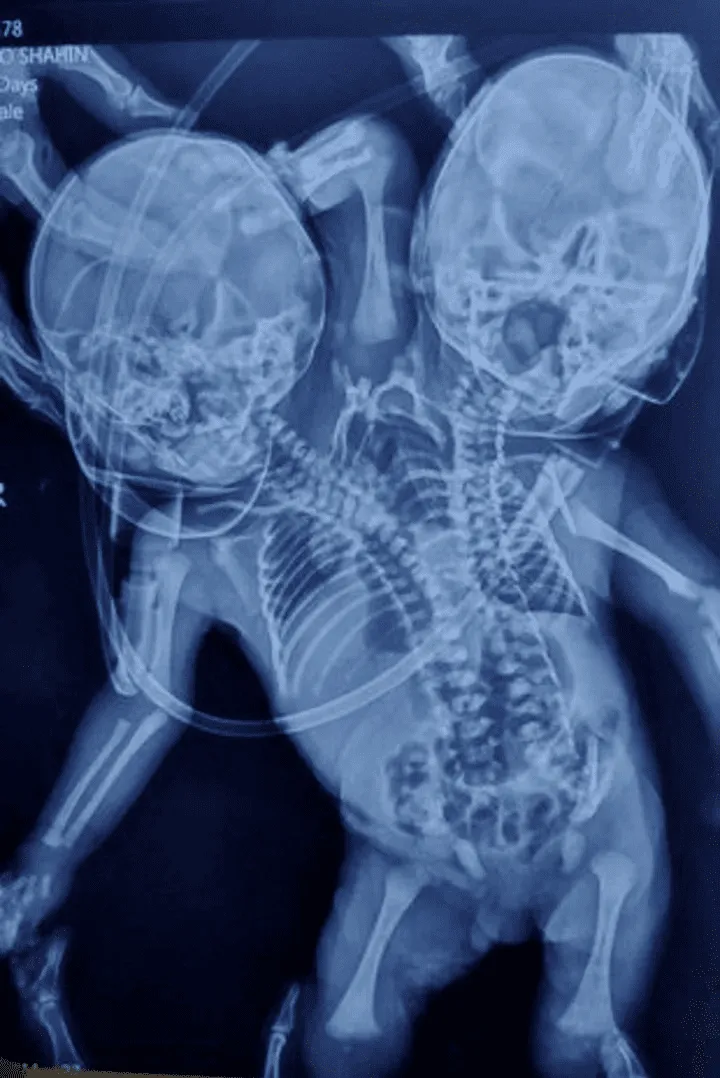

Los médicos de la India quedaron sorprendidos ante un extraño caso: un bebé nació con dos cabezas, tres brazos y dos corazones

La rara condición se llama parapagus dicefálico y es una forma de hermanamiento parcial con dos cabezas de lado a lado en un torso. En este caso, no se había detectado hasta el nacimiento.

El hecho ocurrió el pasado el 28 de marzo en Ratlam, en el estado indio de Madhya Pradesh. Según indicaron medios locales, Shaheen Khan y su esposo Sohail esperaban gemelos y también quedaron atónitos en el momento del parto.

La mayoría de las veces, este nacimiento termina en mortinato, es decir, cuando el bebé muere en el útero durante las últimas 20 semanas del embarazo. Pero tras el "milagro" de haber nacido vivo, los médicos dijeron esperan la evolución y que por ahora no planean una cirugía.

El bebé del milagro fue ingresado en un hospital en la cercana ciudad de Indore para ser monitoreado, mientras que su madre permanece internada en el hospital de distrito de Ratlam.

Hasta el momento, en los informes, no está claro si se considera un nacimiento de gemelos unidos o un niño. Los medios locales lo describen como un bebé, pero la condición se considera una forma rara de gemelos parciales.

Los gemelos unidos son causados por un óvulo fertilizado que comienza a dividirse en dos embriones unas semanas después de la concepción, pero el proceso se detiene antes de que se complete.